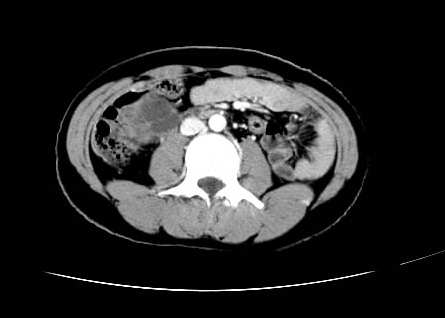

女 16岁  右上腹痛一天,无其他不适

肿块最大径位于十二指肠降段与水平段移行处,并且与肝脏压迹呈“0”形征,可以考虑位于肝外并与胃肠道关系紧密,考虑胃肠道间质瘤(gist)可能较大,须除外神经节起源肿瘤。

肿块与十二指肠关系密切,支持间质瘤诊断.肝脏与结肠均为受压改变.

右下腹巨大肿快,密度不均匀,内见坏死低密度区,边界清楚,与周边胀器明显有分界,未见强化,多考虑来源于间叶组织的良性肿物.

我坚决反对您的观点,该病例定位:横结肠肝曲与升结肠之间的肠系膜及部分肠壁。请看下图:

病灶巨大,少部分向肠腔内生长,大部分向长腔外生长。其密度不均匀,增强显示明显不均匀强化,并见有大片状始终不强化的不规则坏死液化区。虽然病灶中上部形态尚可,病人又如此年轻,但中下部形态、密度、强化特点强烈提示为恶性病灶。综上,我考虑本病例为:恶性胃肠道间质瘤。